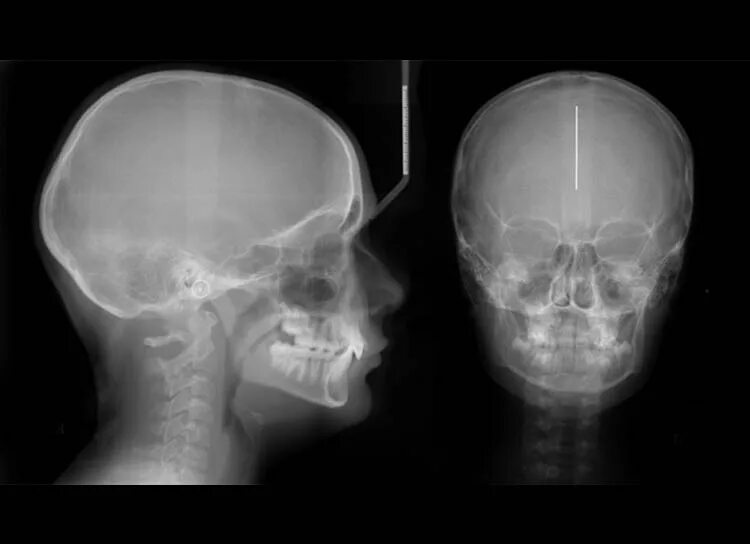

Снимок черепа в прямой проекции